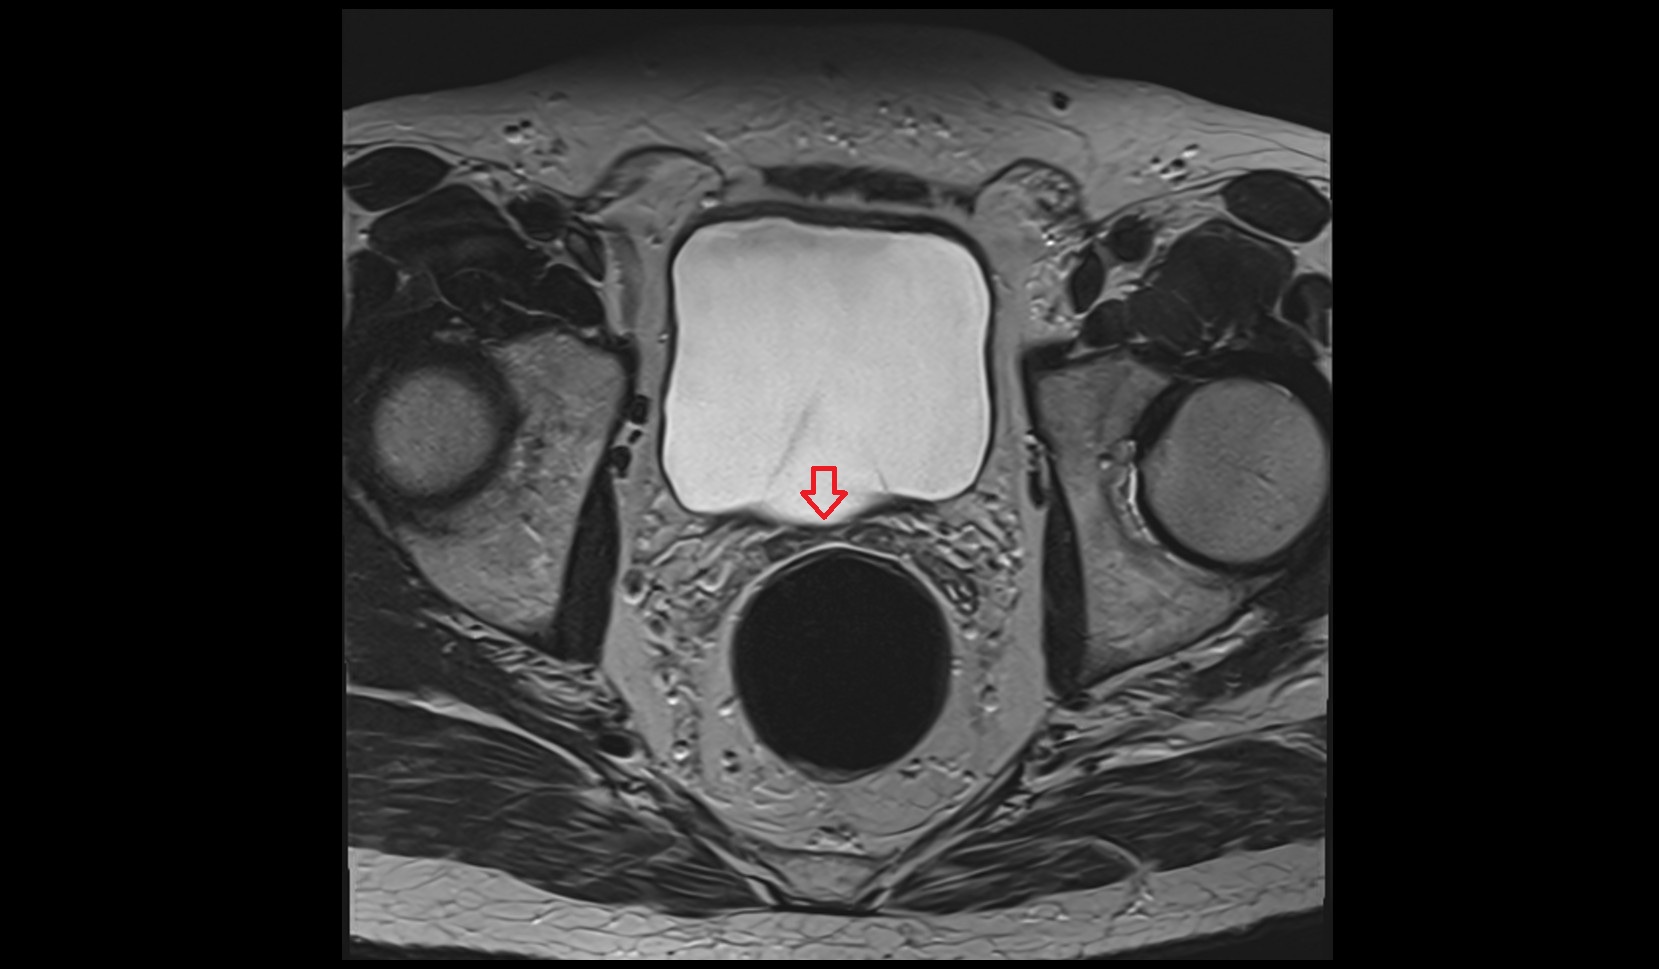

- Peripheral zone of prostate

- Anterior Fibromuscular Stroma of prostate

- Central zone of prostate

- Transitional zone of prostate